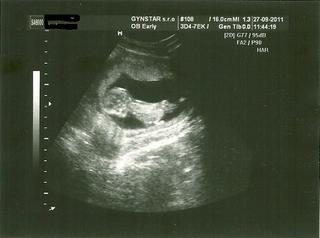

Baby dnes som bola na NT meraní a všetko je v poriadku 😵 a naše bábätko je hotový akrobat...manžel si je istý synom - futbalistom 😀